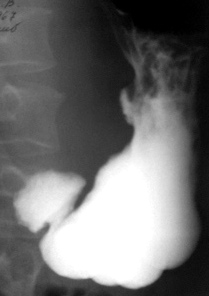

При пальпации за экраном и компресси тубусом и мягким дистинктером вокруг язвенной  ниши определяется выраженный симметричный воспалительный вал – иллюстрация 2.

2.